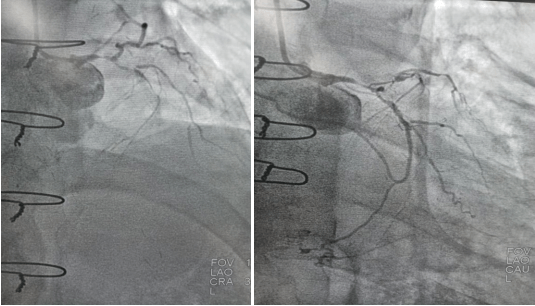

2022年9月16日行冠脈造影術(shù),造影結(jié)果示:左主干末端99%狹窄,LAD近段100%閉塞,LCX開口及近段95%狹窄,乳內(nèi)動(dòng)脈-左前降支血管通暢,RCA近段100%閉塞,大隱靜脈橋血管未見,考慮閉塞。

心血管病院吳棟梁院長(zhǎng)、CCU李新國(guó)副主任、心血管內(nèi)科二病區(qū)趙娟副主任、王端樂主治醫(yī)師、宋睿主治醫(yī)師介入團(tuán)隊(duì)造影后認(rèn)真研究患者的病情和影像資料,決定開通閉塞長(zhǎng)達(dá)11年的右冠狀動(dòng)脈,精確選擇器械,選擇同軸性及支撐力均好的指引導(dǎo)管,術(shù)中選用微導(dǎo)管輔助,軟、硬導(dǎo)絲結(jié)合等技術(shù),聚精會(huì)神、揮汗如雨,終于歷經(jīng)3小時(shí)的努力,成功前向開通右冠狀動(dòng)脈,精準(zhǔn)選擇由遠(yuǎn)及近“鋪設(shè)”通過性較好、長(zhǎng)度合適的支架 。

(術(shù)前術(shù)后對(duì)比)

術(shù)后癥狀明顯改善,活動(dòng)后無胸悶、胸痛,明顯提高患者生活質(zhì)量,提高患者生存率,使患者絕地逢生。